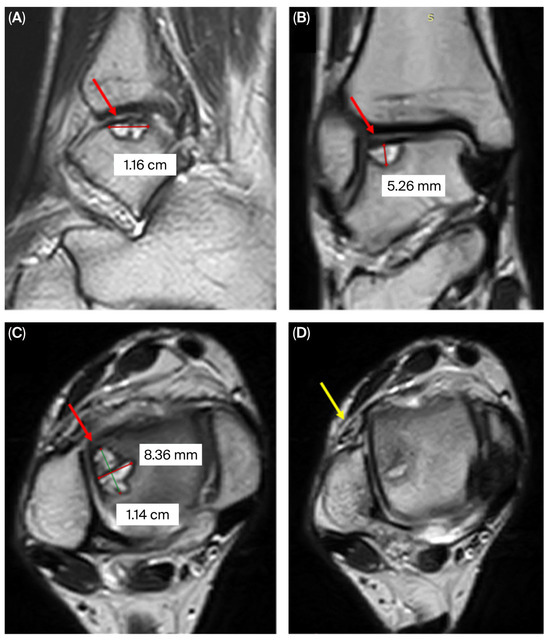

2. Case Presentation